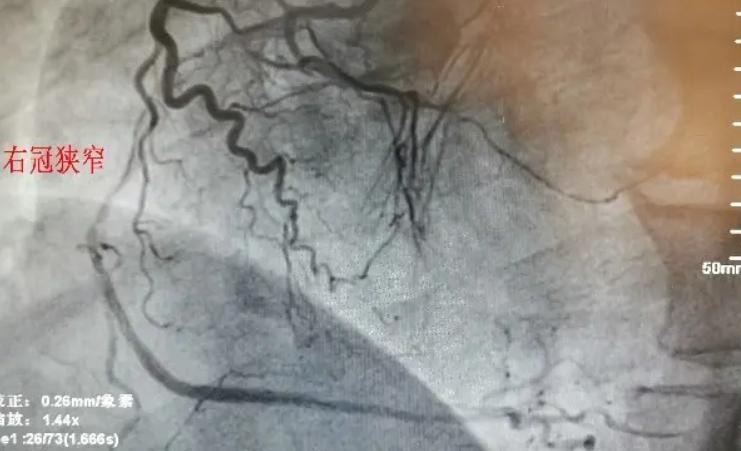

后来我和心内科介入治疗团队经过仔细评估,并做好了各种应急措施后,为老人完成了冠脉造影检查。结果显示,确实是冠心病,冠脉血管有狭窄病变,但血流并未明显受影响,因此没有进行植入支架等治疗。适当药物治疗后,老人的病情得到明显改善。

而冠脉造影是一种微创介入检查。通过冠脉造影,可以探知冠状动脉中有没有狭窄现象以及狭窄的情况,然后根据实际情况,对狭窄部位进行针对性治疗。可以说,冠脉造影是诊断冠心病的金标尺!

在冠脉造影检查中,患者首先需要平卧在导管室的手术床上,大多选择右手桡动脉为穿刺点,局部麻醉后进行桡动脉穿刺,将一根很细的导管经桡动脉入口一直伸入到主动脉根部,找到冠脉开口,通过导管将造影剂注入冠脉,X光下就能看到冠脉有无狭窄或阻塞。